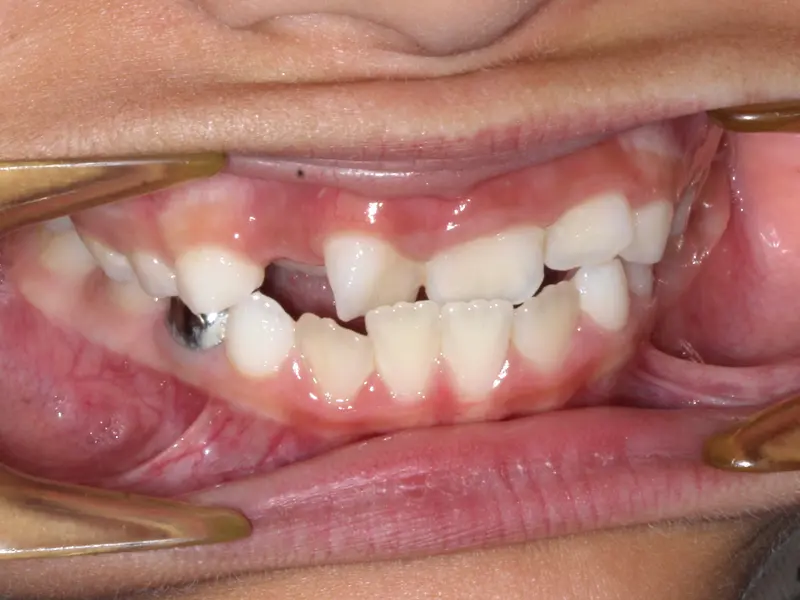

After treatment: Complex Bite Correction

After

Before treatment: Complex Bite Correction

Before

Anterior Open Bite with Class III tendency (Underbite). The front teeth did not touch, making chewing difficult and placing excessive force on the back teeth.

Using Invisalign with "SmartForce" attachments, we intruded the posterior teeth (molars) to close the bite at the front. We simultaneously corrected the underbite relationship using precision-cut elastics, achieving full function without surgery.